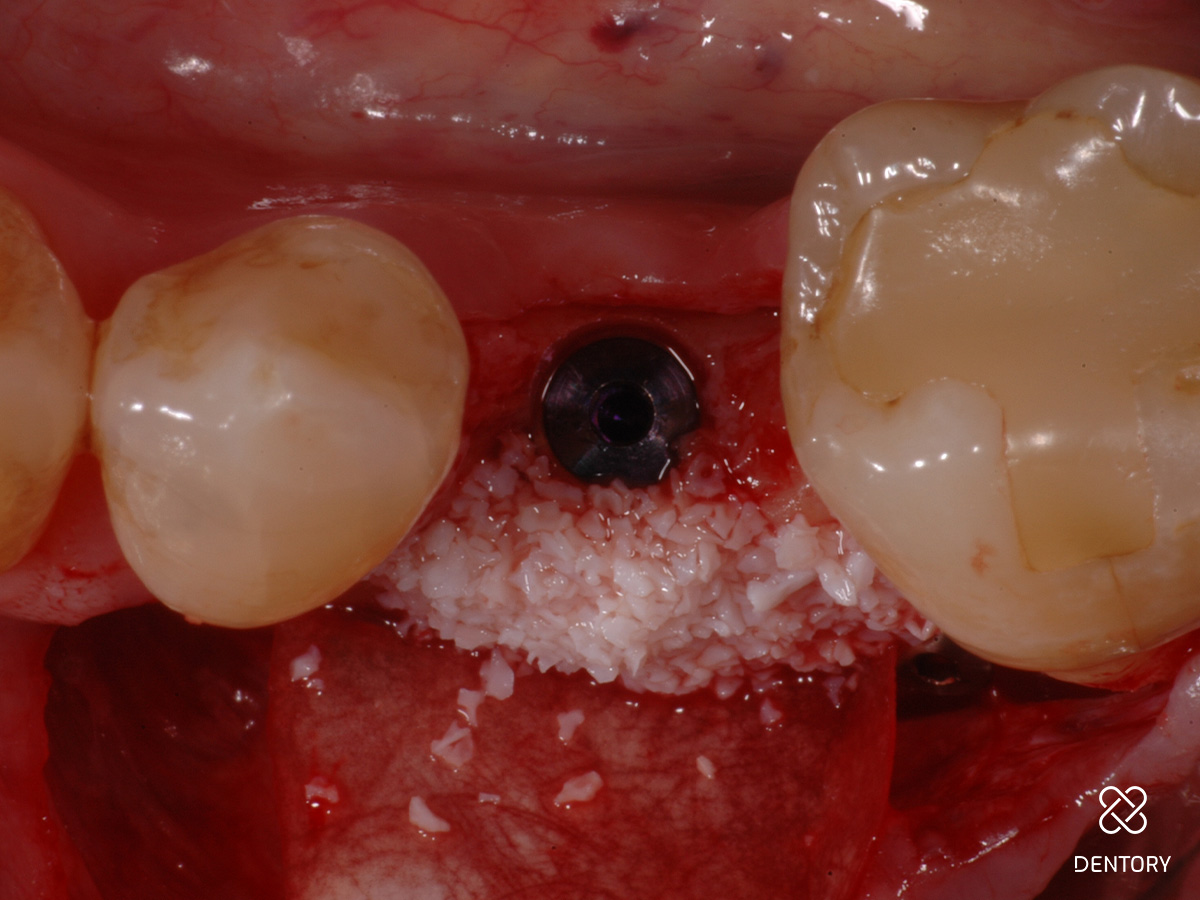

Abbildung 6

Der Knochendefekt wird mit einem resorbierbaren xenogenen Knochenersatzmaterial aufgefüllt, sodass die ursprüngliche Kammanatomie wieder hergestellt wird.